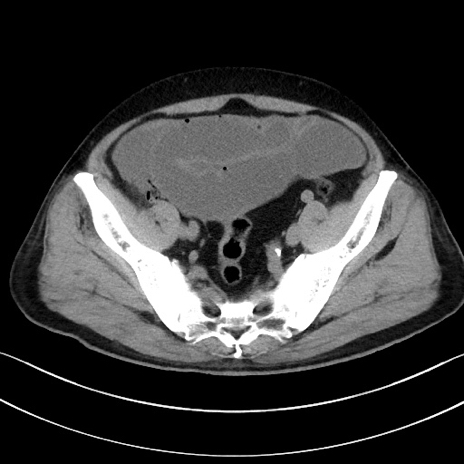

症例15(横断像)

【症例】70歳代男性

【主訴】腹痛

【現病歴】今朝から腹痛あり。全体的に痛い。特に左上の方。排ガスが今日はない。冷や汗が出る。

【既往歴】直腸癌術後

【身体所見】左側腹部〜上腹部に圧痛あり。腹膜刺激症状明らかなではない。軽度反跳痛。左下腹部に術後瘢痕あり。

【データ】WBC 7700、CRP 0.02